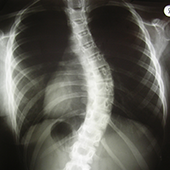

A gerincferdülés nagyságát az ún. Cobb-fokkal mérjük: ez a görbületben résztvevő kezdő-, és végcsigolyák zárólemezére húzott egyenesek által bezárt szög kiegészítő szöge.

Scheuermann dán sebészről kapta a nevét, aki a röntgenfelvételen jellegzetes csigolyaszerkezeti eltéréseket talált.

A betegség a gerinc bármelyik szakaszán előfordulhat és ennek megfelelően különböző elváltozások jönnek létre. Leggyakrabban a háti szakaszon jelentkezik a betegség, itt a fokozott háti domborulat, ún. kerekhát deformitás jön létre. Ha a betegség az ágyéki szakaszon fordul elő, akkor az élettani görbületek elsimulnak, és ún. laposhát vagy botgerinc alakul ki. A betegség területén a gerincszakasz mozgása korlátozott, spontán fájdalom, fáradékonyság, nyomásérzékenység jelentkezhet. A röntgenen található jellegzetes elváltozások: a csigolyatest elülső része laposabbá válik (ún. ékcsigolya), a zárólemez és a porckorong elváltozásai következtében kis csomócskák (Schmorl-csomók) láthatóak a röntgenképen.

Röntgenvizsgálat:

Ha a gerinc szagittális görbületeinek fent leírt változásait észleljük, feltétlenül szükséges a kétirányú gerincfelvétel. A röntgenfelvétel alapján lehet eldönteni, hogy hanyag tartásról vagy Scheuermann-kórról van-e szó. Álló helyzetben az egész gerincről készült felvétel jól mutatja a görbületek nagyságát és elhelyezkedését. Fekvő helyzetben a gerinc mobilitását, rugalmasságát tudjuk vizsgálni.